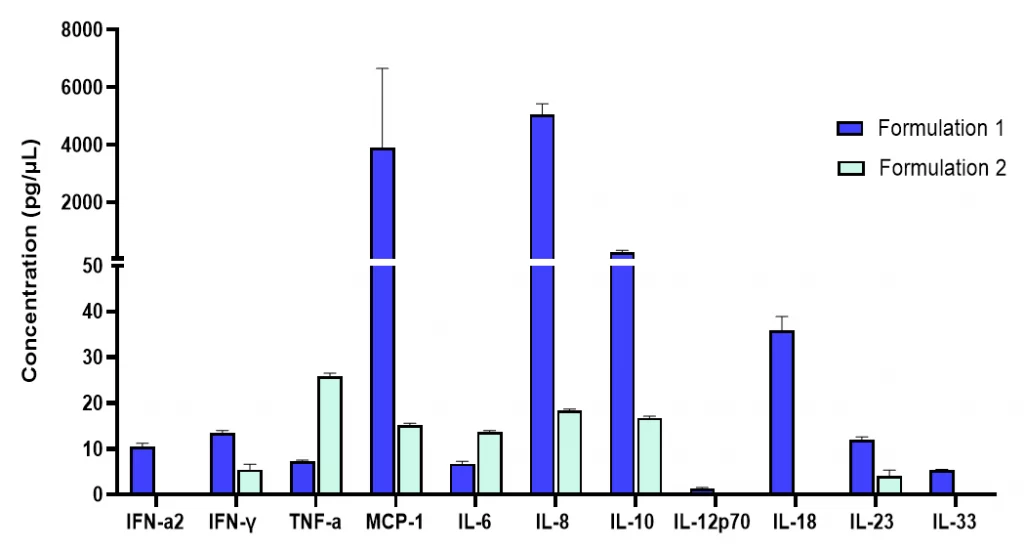

Fig 3: Pro-inflammatory cytokines release by human PBMCs were measured in response to different drug formulation stimulations.

Human PBMCs were plated in triplicate at a density of 2.5 × 105 cells/well and incubated with Test Compounds for 6 hours at 37 °C. Cell culture supernatants were removed and analyzed with fluorescence bead-based multiplex cytokine assay (LEGENDplex™ Human Inflammation Panel 1) using Flow Cytometry.